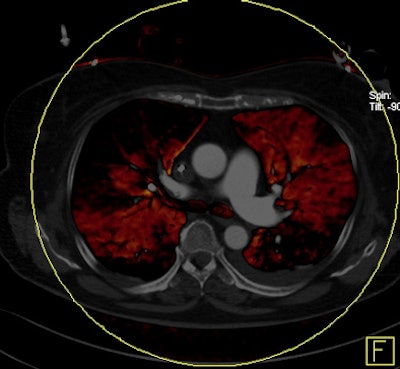

Dual-energy CT enables the selective display of iodine distribution within the pulmonary parenchyma following contrast-enhanced pulmonary CT angiography, which in turn permits the calculation of perfusion defect (PD) size in patients with suspected PE.

Depending on the shape and pattern of the defects at dual-energy CT, perfusion defects due to PE can generally be distinguished from, for example, patchy defects signaling other pathologies of the lung parenchyma, Bauer said.

The researchers measured perfusion defect size in the lung parenchyma caused by PE on dual-energy iodine distribution maps, and expressed it in two ways: as absolute quantification (VolPD in mL) and relative to the total lung volume (RelPD in %).

| Patient with bilateral segmental and subsegmental PE and large perfusion defects on dual-energy iodine distribution maps. All images courtesy of Dr. Ralf Bauer. |